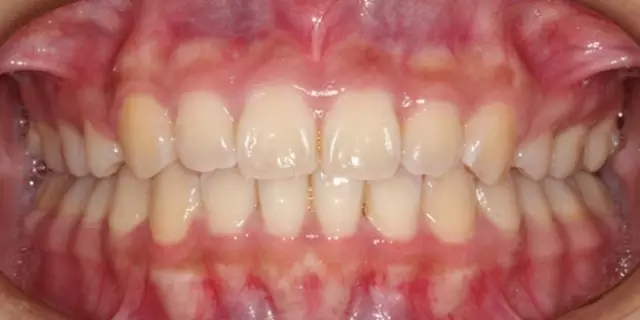

Damon 病例分享:安氏 II 類二分類露齦笑的矯治(董一磊)

治療前后對比